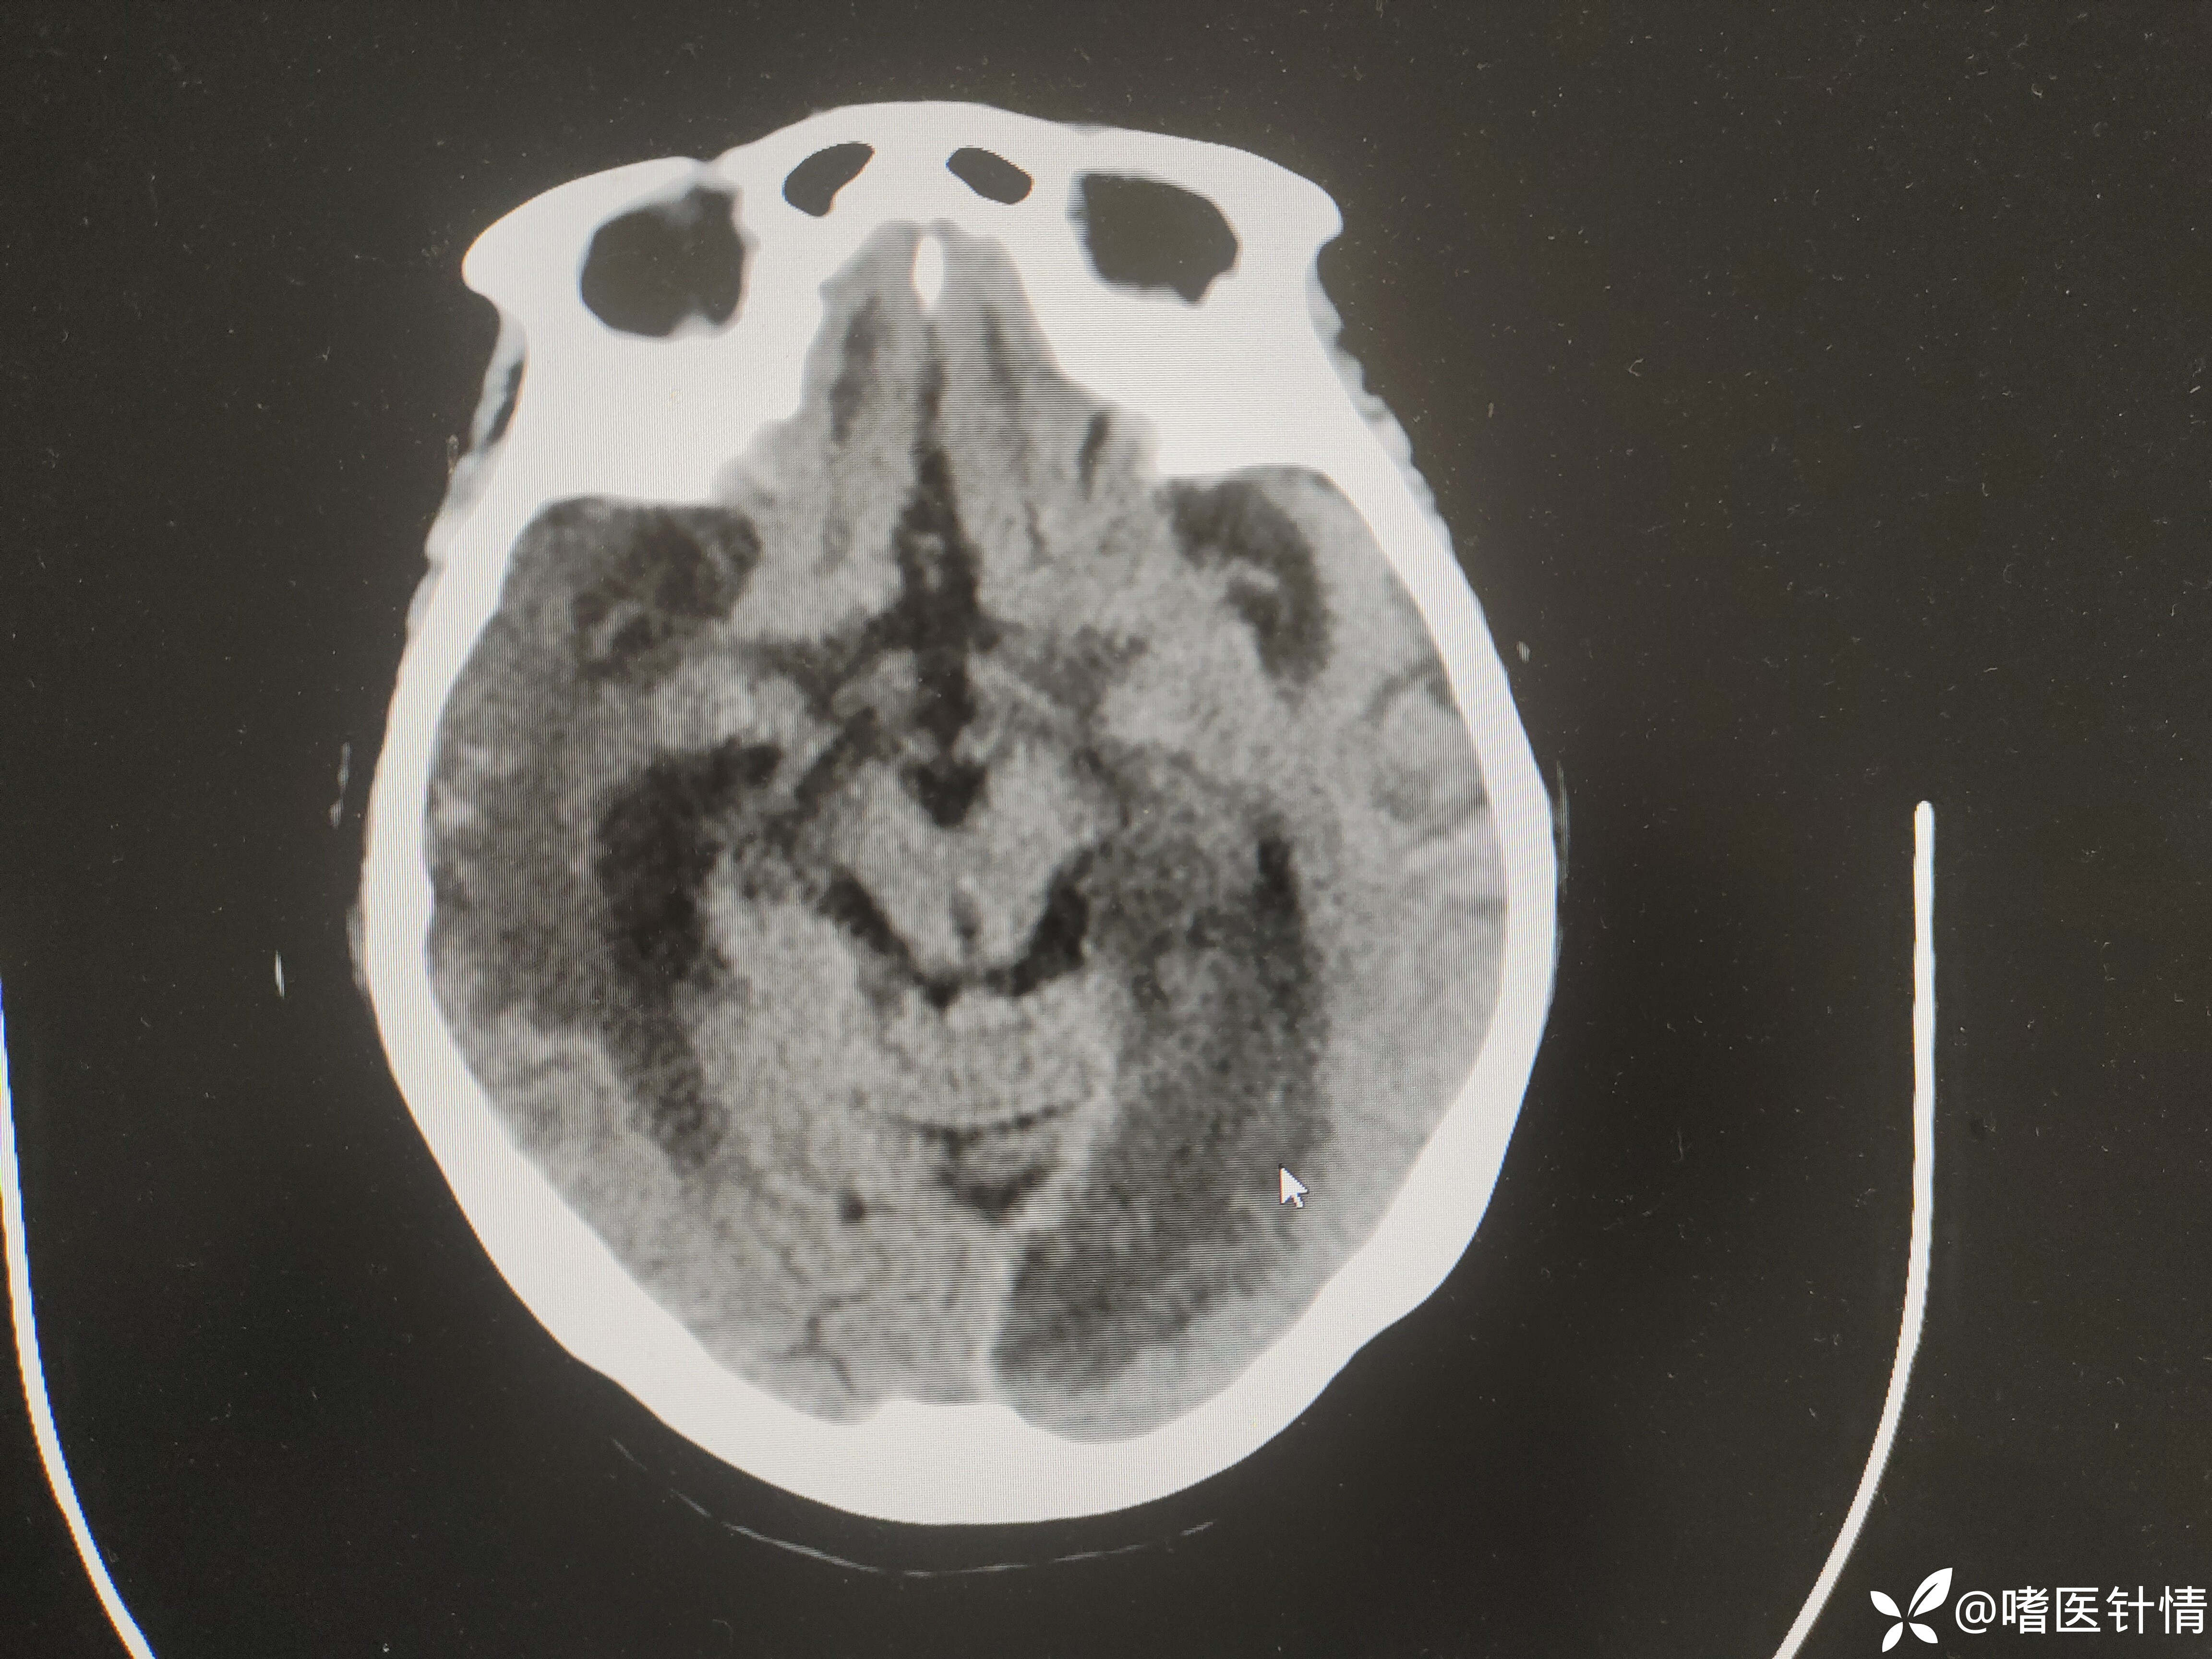

【治疗经过及结果】:给我抗凝,3个月后呼吸困难,再次复查头颅CT见

患者房颤,引起脑栓塞,给予低分子肝素抗凝,脑保护治疗,患者三个月后再次病情加重。